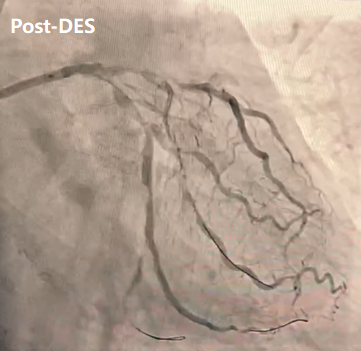

冲击波治疗:使用3.0×12mmIVL多次预处理LAD近中段病变。

支架植入后造影:支架膨胀、贴壁满意。行IVUS示LAD支架贴壁良好,无夹层撕裂。最终FFR值达0.96,充分满足血运重建的生理学评估指标,证实了手术策略与器械应用的精准有效。